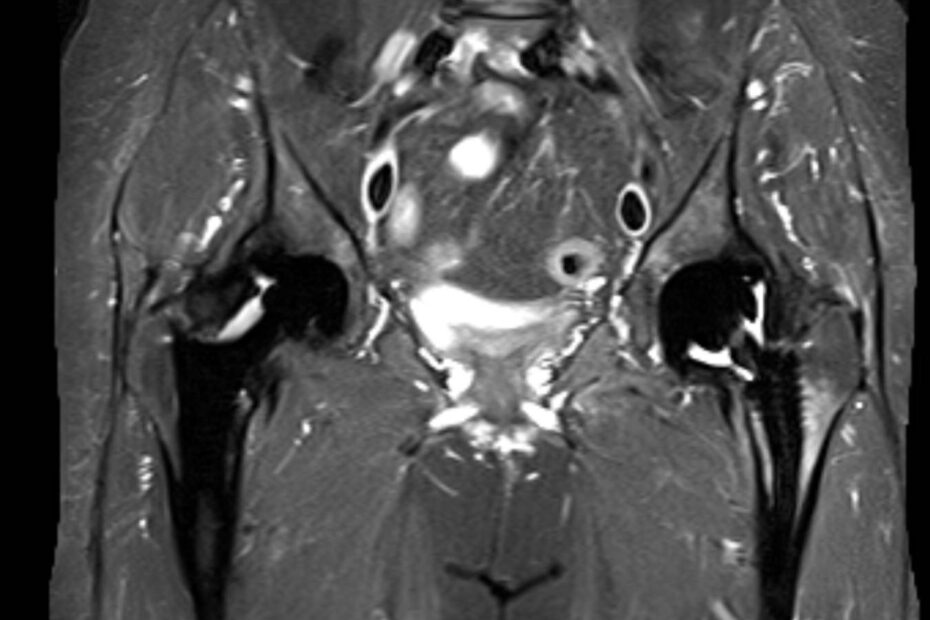

Die Magnetresonanztomographie des Beckens, kurz MRT Becken genannt, ermöglicht es den Bereich des Beckens bildlich darzustellen. Hierbei ist nicht nur der knöcherne Teil des Beckens zu sehen, sondern auch Gelenke und insbesondere Organe, die sich im Beckenbereich befinden. Die MRT Becken ermöglicht strahlenfreie und präzise Bildgebung. Das Becken ist die zentrale Verbindung zwischen unseren Beinen … MRT Becken weiterlesen